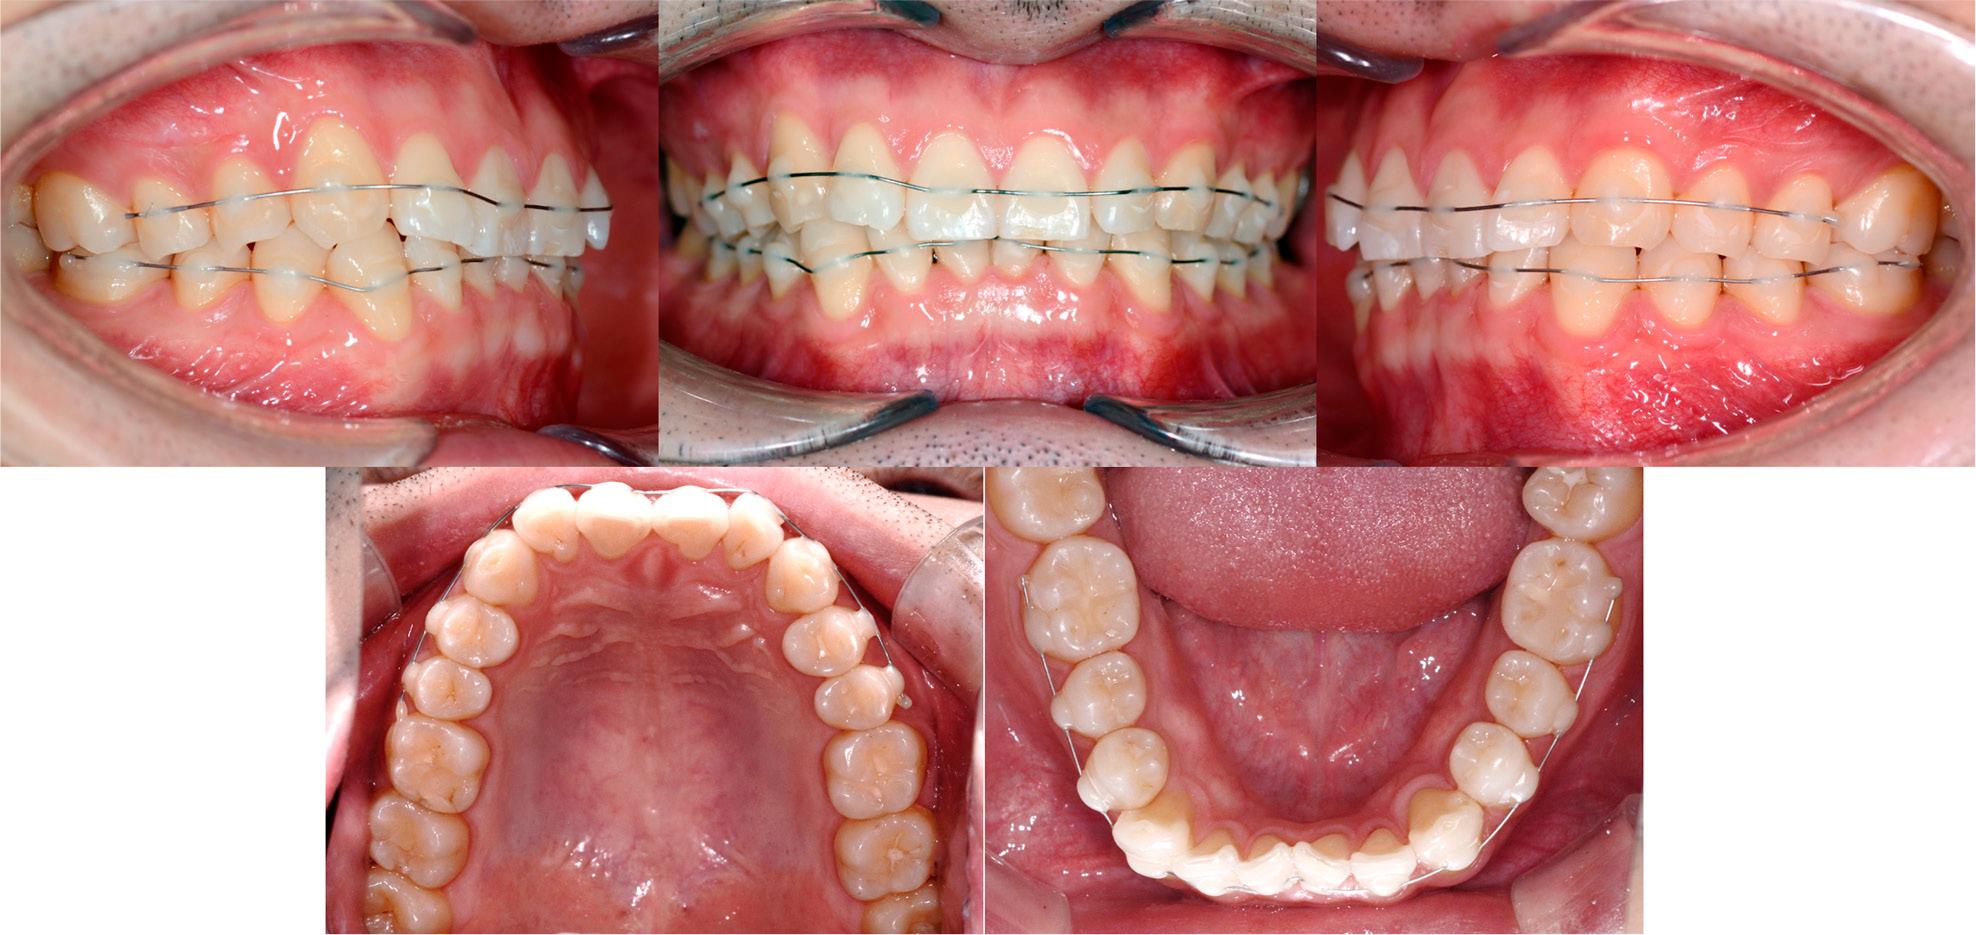

NiTi wires (0.014-inch, DynaFlex, MO, USA) were bonded to the maxillary and mandibular arches using flowable resin (Tetric® N-Flow, Ivoclar Vivadent, Schaan, Liechtenstein). To ensure play between the wire and bracket, a lubricant was applied on the wire before bonding. To enhance alignment, labial proclination of the anterior teeth was generated which modified the arch form into an ovoid shape (Figure 3). As treatment progressed, the archwire bonding was continually adjusted. After eight months, the alignment of the maxillary dentition had improved (Figure 4). However, the distal angulation of the mandibular canines was evident, as the right side remained the most prominent.

Intraoral photographs after the bonding of bracketless nickel-titanium wires.